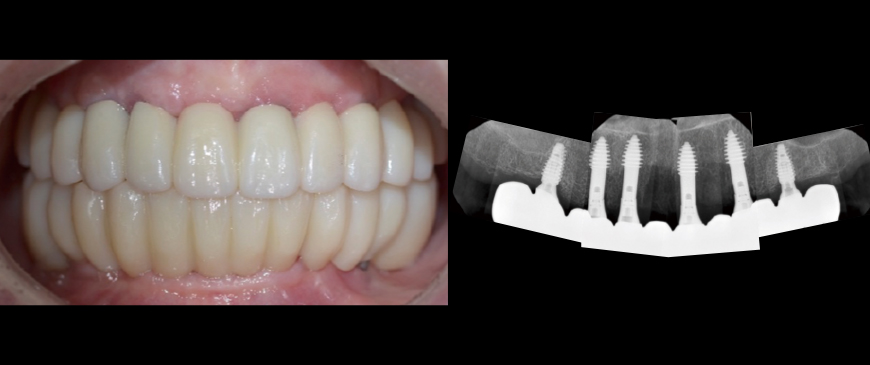

Custom abutments and PMMA temporary restorations were placed on the entire maxillary implants. The condition was stable both aesthetically and functionally.

Fig 9

Approximately 6 months after the maxillary surgery, the final prostheses were placed on both the upper and lower implants. The FP1 (Functional Prosthesis 1) was successfully achieved on a thin ridge, utilizing a minimally invasive approach and a short treatment period. This was accomplished without sacrificing the integrity of the thin ridge or requiring heavy GBR.